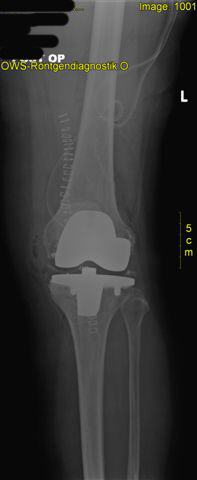

postoperatives Röntgen mit korrektem Sitz der Knieprothese